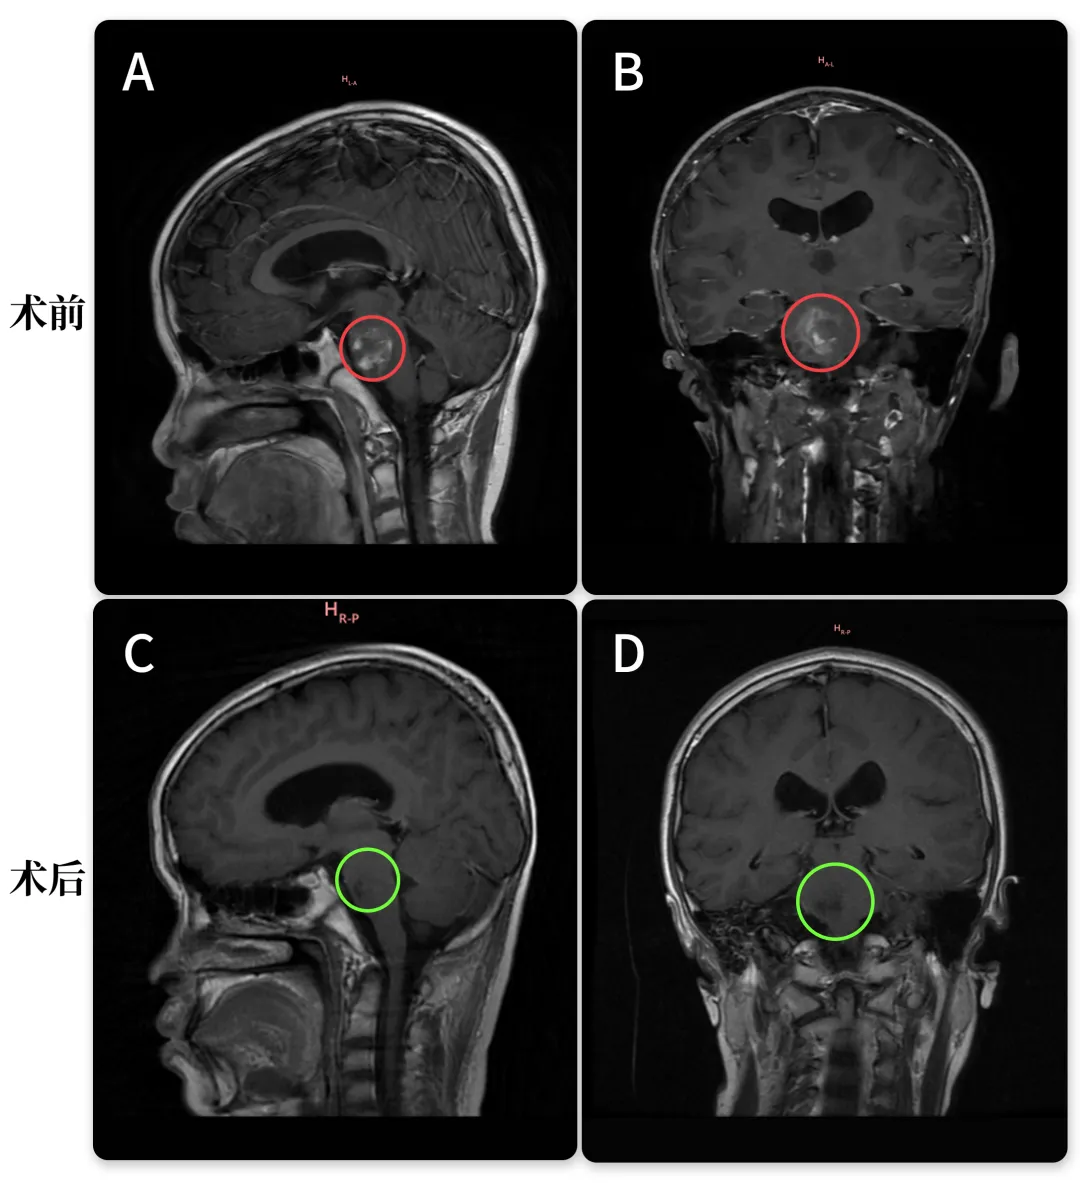

术后半年,我们找巴教授随访过一次,因为当时复查核磁上说脑干有异常信号,考虑海绵状血管瘤,我的心一下子提到嗓子眼,连忙约了跟教授远程随访,好在是虚惊一场。

教授说不存在残留,当然也没有海绵状血管瘤复发。其实这是含铁血黄素的残留,对于巨大出血性的内生性脑干病变是正常的,并不是活跃性海绵状血管瘤。